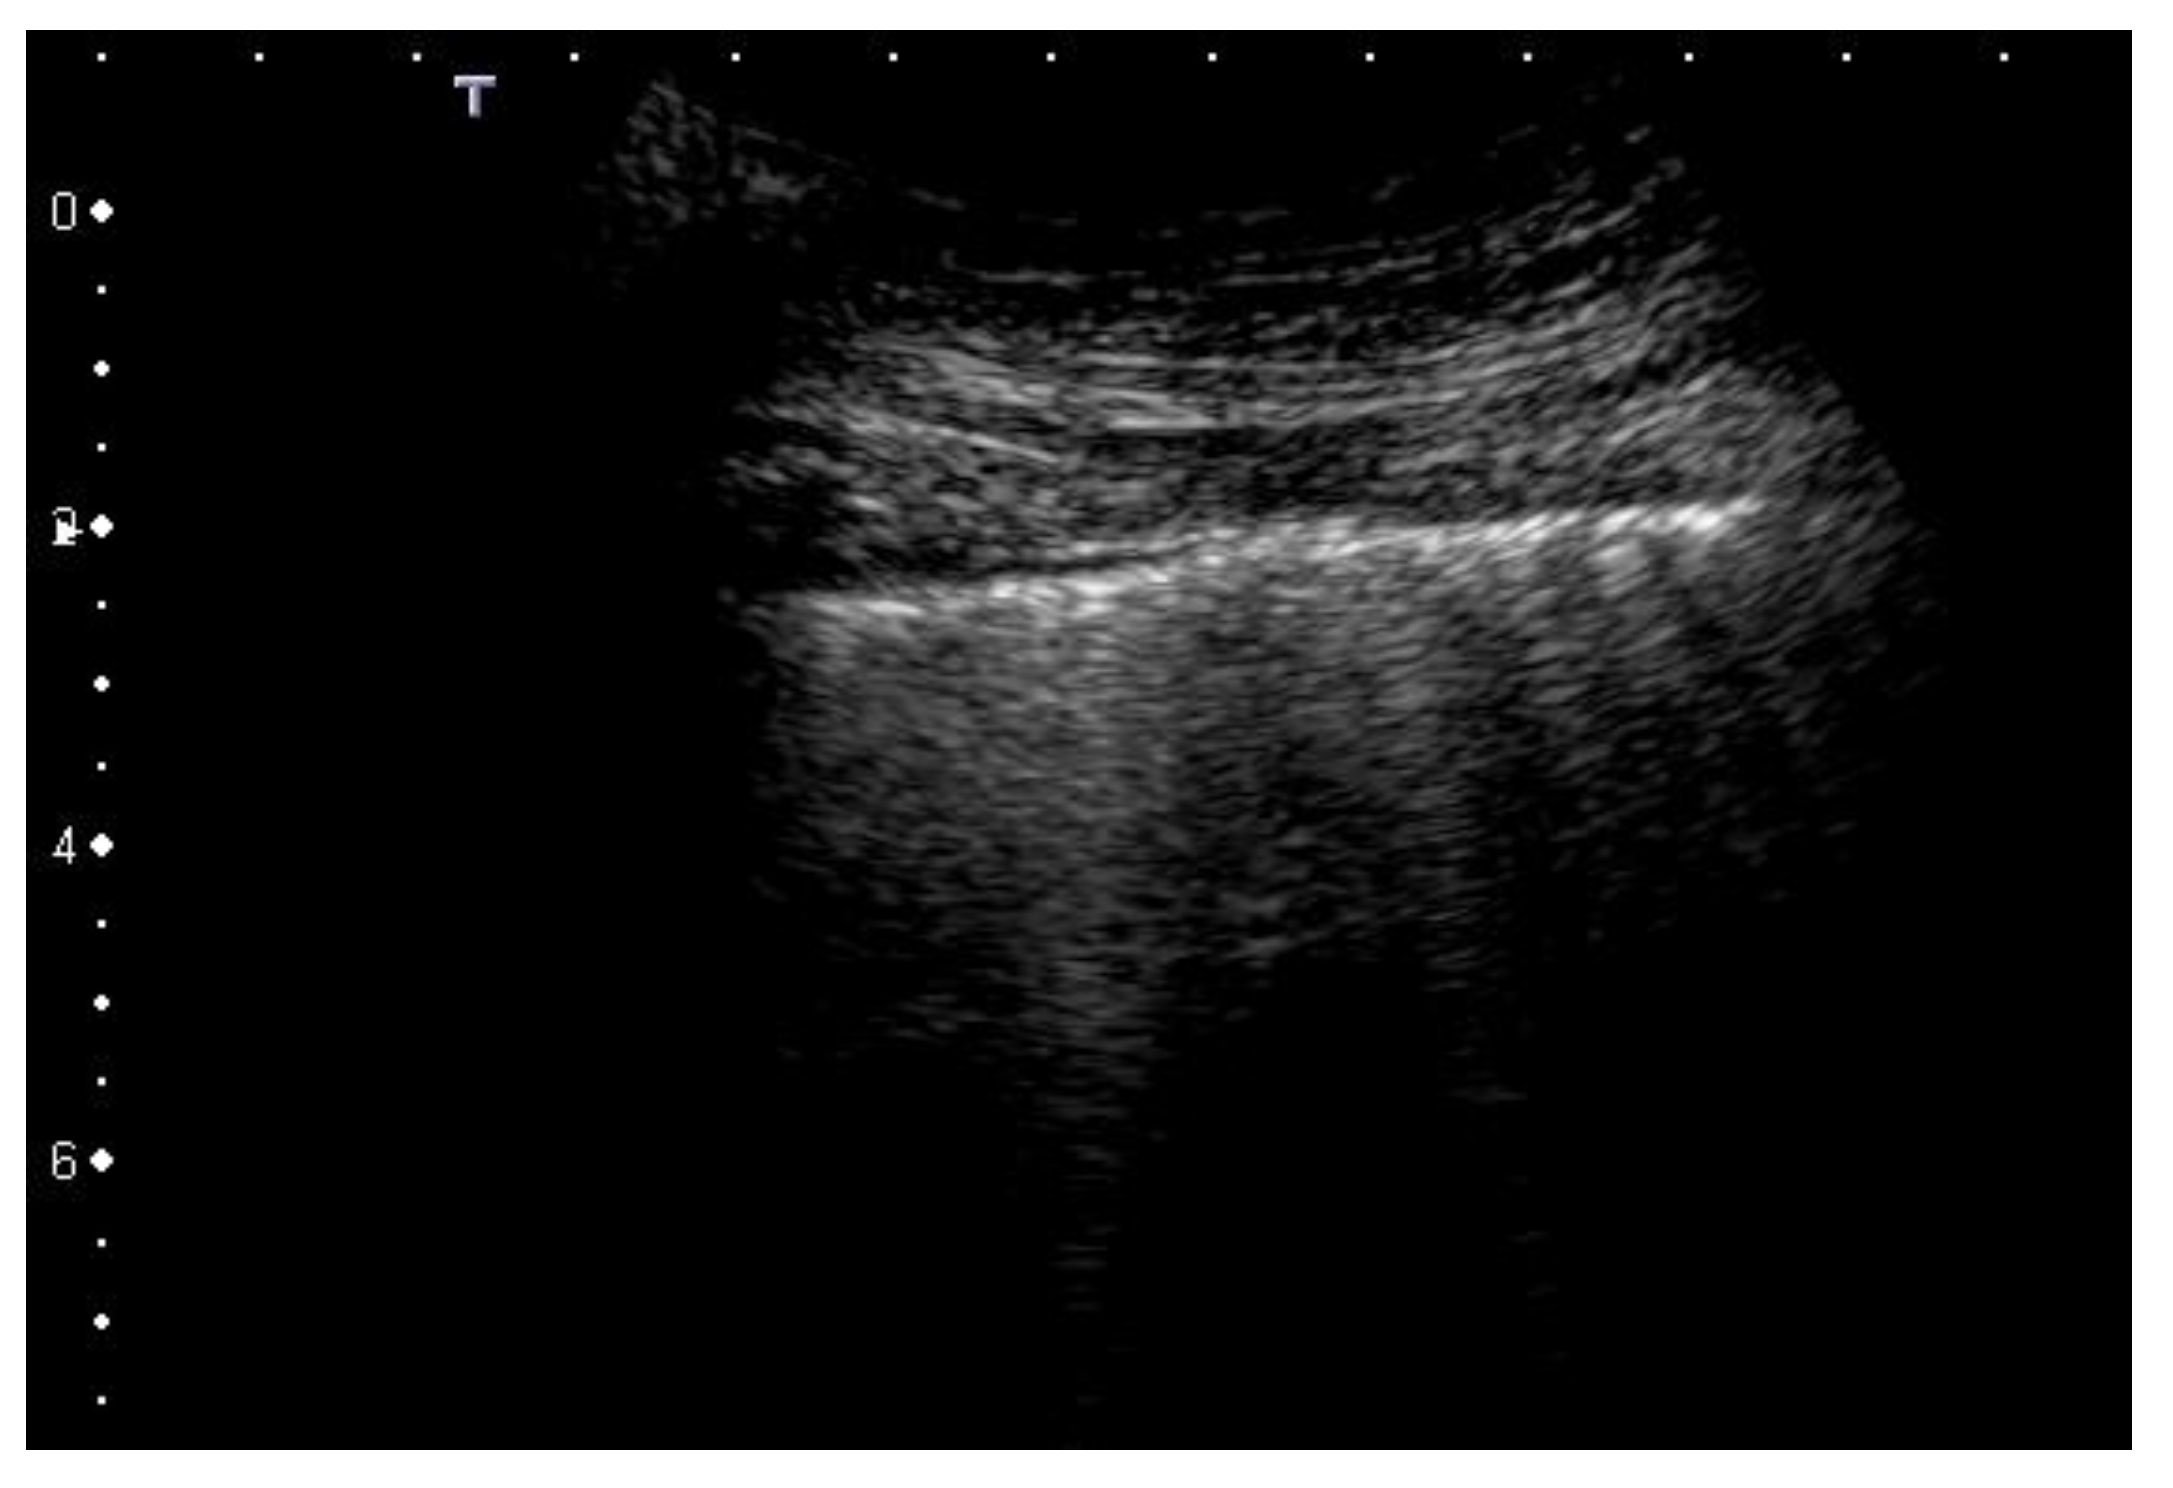

A-lines are horizontal artifacts related to a normal pleural plane. A-lines are a replica of the pleural line and a blurred superposition of the parietal acoustic discontinuities appears between the pleura line and the first A-line (as well as between every pair of subsequent A-lines) due to the mirror and replica effects caused by the strong reflection of the pleural line [7], (Figure 1). This pattern represents how ultrasound scanners visualize the echo signals that are bouncing between the probe, the chest wall planes, and the lung surface.

Figure 1. Normal lung. Pleural line is regular. The first artefactual replica of the pleural line is clearly seen (deeper arrow). Between the pleural line and the first A-line, a blurred superposition of the parietal acoustic discontinuities appears due to the mirror and replica effects caused by the strong reflection of the pleural line. Linear probe, 8 MHz.